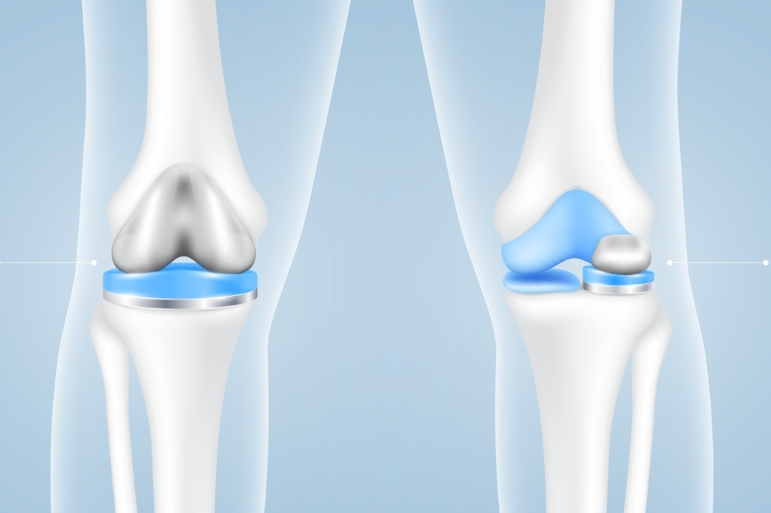

Στις αρχές της δεκαετίας του 1970 παρουσιάστηκε ένας σχεδιασμός αρθροπλαστικής γόνατος γνωστός ως «ολικό εμφύτευμα κονδύλων». Αυτό περιλάμβανε την τοποθέτηση ενός μεταλλικού καλύμματος γύρω από το κατώτερο τμήμα του μηριαίου και μιας πλαστικής επιφάνειας στο ανώτερο τμήμα της κνήμης. Η πλαστική επιφάνεια ήταν έτσι διαμορφωμένη για να μιμείται την φυσιολογική αρθρική επιφάνεια της κνήμης ώστε να επιτρέπει στην άρθρωση να κάμπτεται, να εκτείνεται και να στρίβει.

Η διατήρηση των χιαστών συνδέσμων, κυρίως του οπίσθιου χιαστού, κατά την αντικατάσταση του γόνατος, αποτέλεσε επίσης για πολλά χρόνια σημαντική παράμετρο στον σχεδιασμό της επέμβασης. Ένας αριθμός μοντέλων ολικής αρθροπλαστικής γόνατος επίσης άφηναν τον πρόσθιο χιαστό σύνδεσμο άθικτο, αλλά δε χρησιμοποιούνται πλέον ευρέως.

Σχετικά με την αφαίρεση του οπίσθιου χιαστού συνδέσμου δεν είναι τόσο κακό όσο ακούγεται. Αναλυτικότερα, μια ολική αρθροπλαστική γόνατος χωρίς χιαστούς συνδέσμους είναι καλύτερη από ένα αρθριτικό γόνατο με χιαστούς. Τα τεχνητά εμφυτεύματα είναι σχεδιασμένα έτσι ώστε να λαμβάνουν υπόψη τους την έλλειψη των χιαστών και να την αντιρροπούν. Για τον λόγο αυτό, το πλαστικό εμφύτευμα της κνήμης διαθέτει ειδική προεξοχή που μιμείται τη λειτουργία του οπίσθιου χιαστού συνδέσμου, ενισχύοντας τη σταθερότητα της άρθρωσης.

Στις μέρες μας η αντικατάσταση ή όχι του οπίσθιου χιαστού αποτελεί αντικρουόμενο ζήτημα μεταξύ των ορθοπαιδικών. Υπάρχουν σχολές που αντικαθιστούν τον οπίσθιο χιαστό και αυτές που τον διατηρούν. Κάθε σχολή έχει τα επιχειρήματά της.

Φωτογραφία 2η : Ολική αρθροπλαστική γόνατος